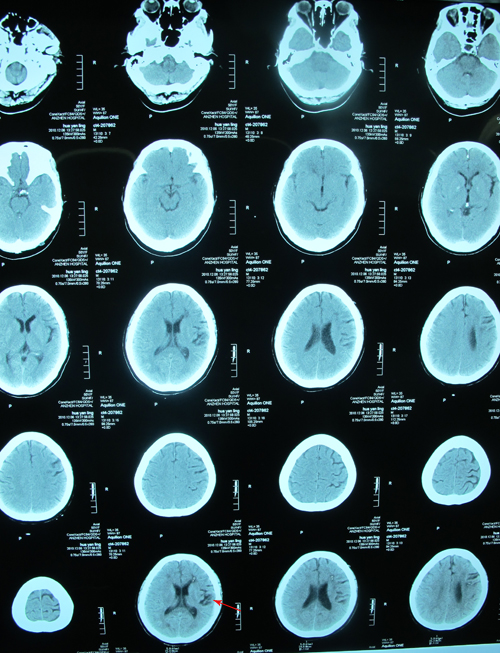

头颅MRA(2010-10-31):右侧颈内动脉狭窄,左侧大脑前动脉、大脑中动脉未显影。